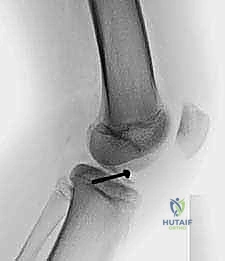

2. التصوير بالأشعة السينية (X-rays)

هي الخطوة الأولى والأساسية. يطلب الدكتور هطيف صوراً بأوضاع متعددة:

* صورة أمامية خلفية (AP): لرؤية الهيكل العام.

* صورة جانبية (Lateral): وهي الأهم لرؤية شوكة الظنبوب وتقييم درجة ارتفاعها وإزاحتها (لتحديد تصنيف مايرز ومكيفير).

* صورة النفق (Tunnel View): لرؤية الشق بين اللقمتين بوضوح.